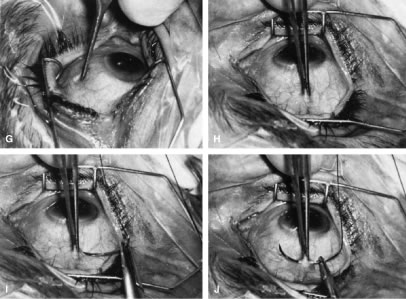

To obtain increasingly lower IOP, it is necessary to modify surgical technique (Table 15). By performing guarded filtration procedures so that the sutures can be released postoperatively, with the use of either laserable or releasable sutures, a lower final IOP can be obtained in some cases. This technique allows a bleb to develop that is similar to that seen in a full-thickness filtration procedure. Such blebs tend to be thin, polycystic, and located directly at the limbus, in contrast to those seen after classic trabeculectomy, which are thicker, lower, more diffuse, and more posterior. When antifibrosis agents (antimetabolites and corticosteroids) are added to procedures designed to develop full-thickness filtration, IOP tends to be sharply reduced.27–29 The blebs associated with the use of 5-fluorouracil (5-FU) and mitomycin are an exaggeration of the full-thickness type of bleb: Often, they are extensive, sometimes involving 360 degrees of the anterior surface of the globe, and the conjunctiva tends to be thin and completely ischemic.30–34

If the decision has been made to perform surgery, the surgeon must consider how to perform the surgery to achieve the desired target pressure range (see Table 14). Although it is not always possible to achieve the desired target pressure range, certain procedures and approaches to surgery give the surgeon the ability to approximate the goal. A guarded filtration procedure performed essentially as described by Watson, for example, in a white patient without risk factors for failure usually will result in IOP of approximately 17 mm Hg, ranging from 15 to 19 mm Hg.26 In contrast, a full-thickness filtering procedure, such as a corneoscleral trephine, usually will result in a mean IOP of approximately 14 mm Hg, with a range of 12 to 16 mm Hg.26